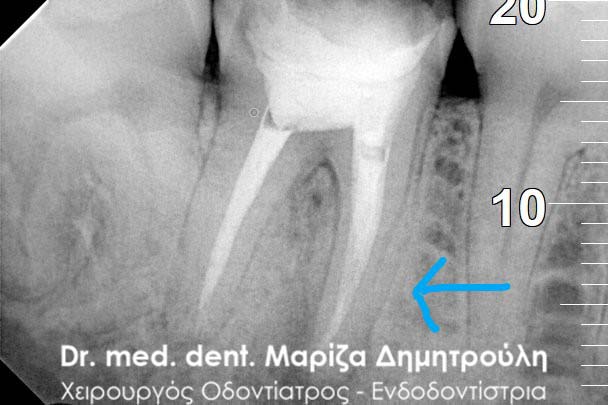

Root canal retreatment

BEFORE

BEFORE